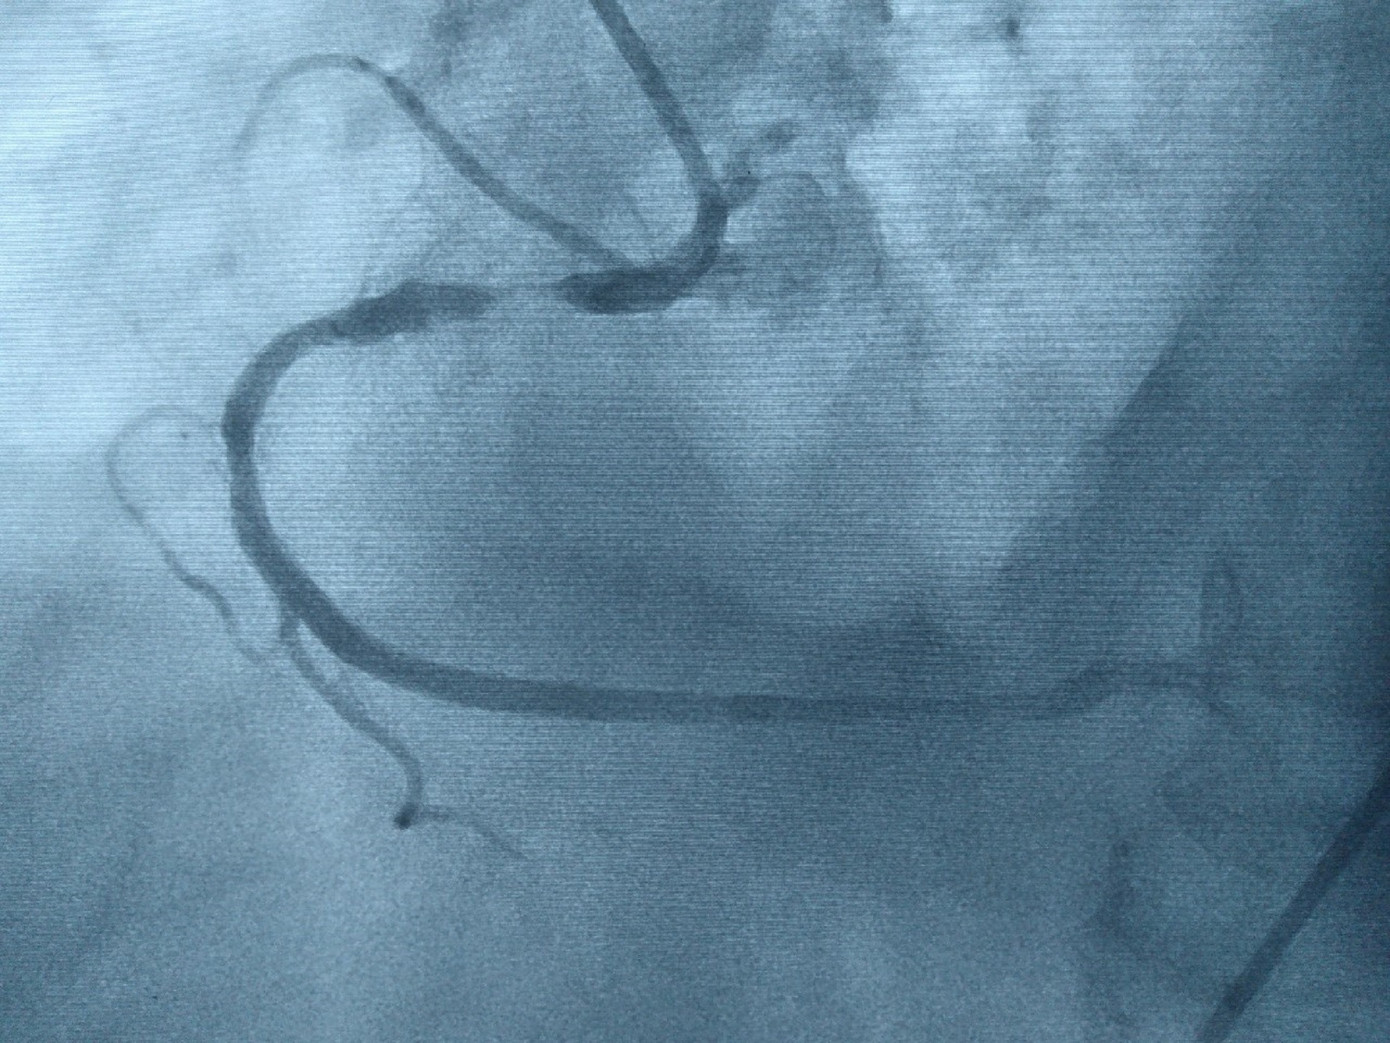

![]() |

| Hình ảnh động mạch vành bị hẹp nặng |